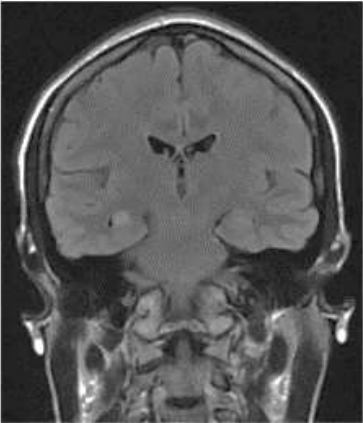

Mulher de 26 anos apresenta múltiplas crises focais disperceptivas, de início focal com automatismos. Em investigação clínica, vista imagem de crânio (imagem).

Ressonância magnética de crânio

Em relação à condição clínica da paciente, assinale a alternativa correta.